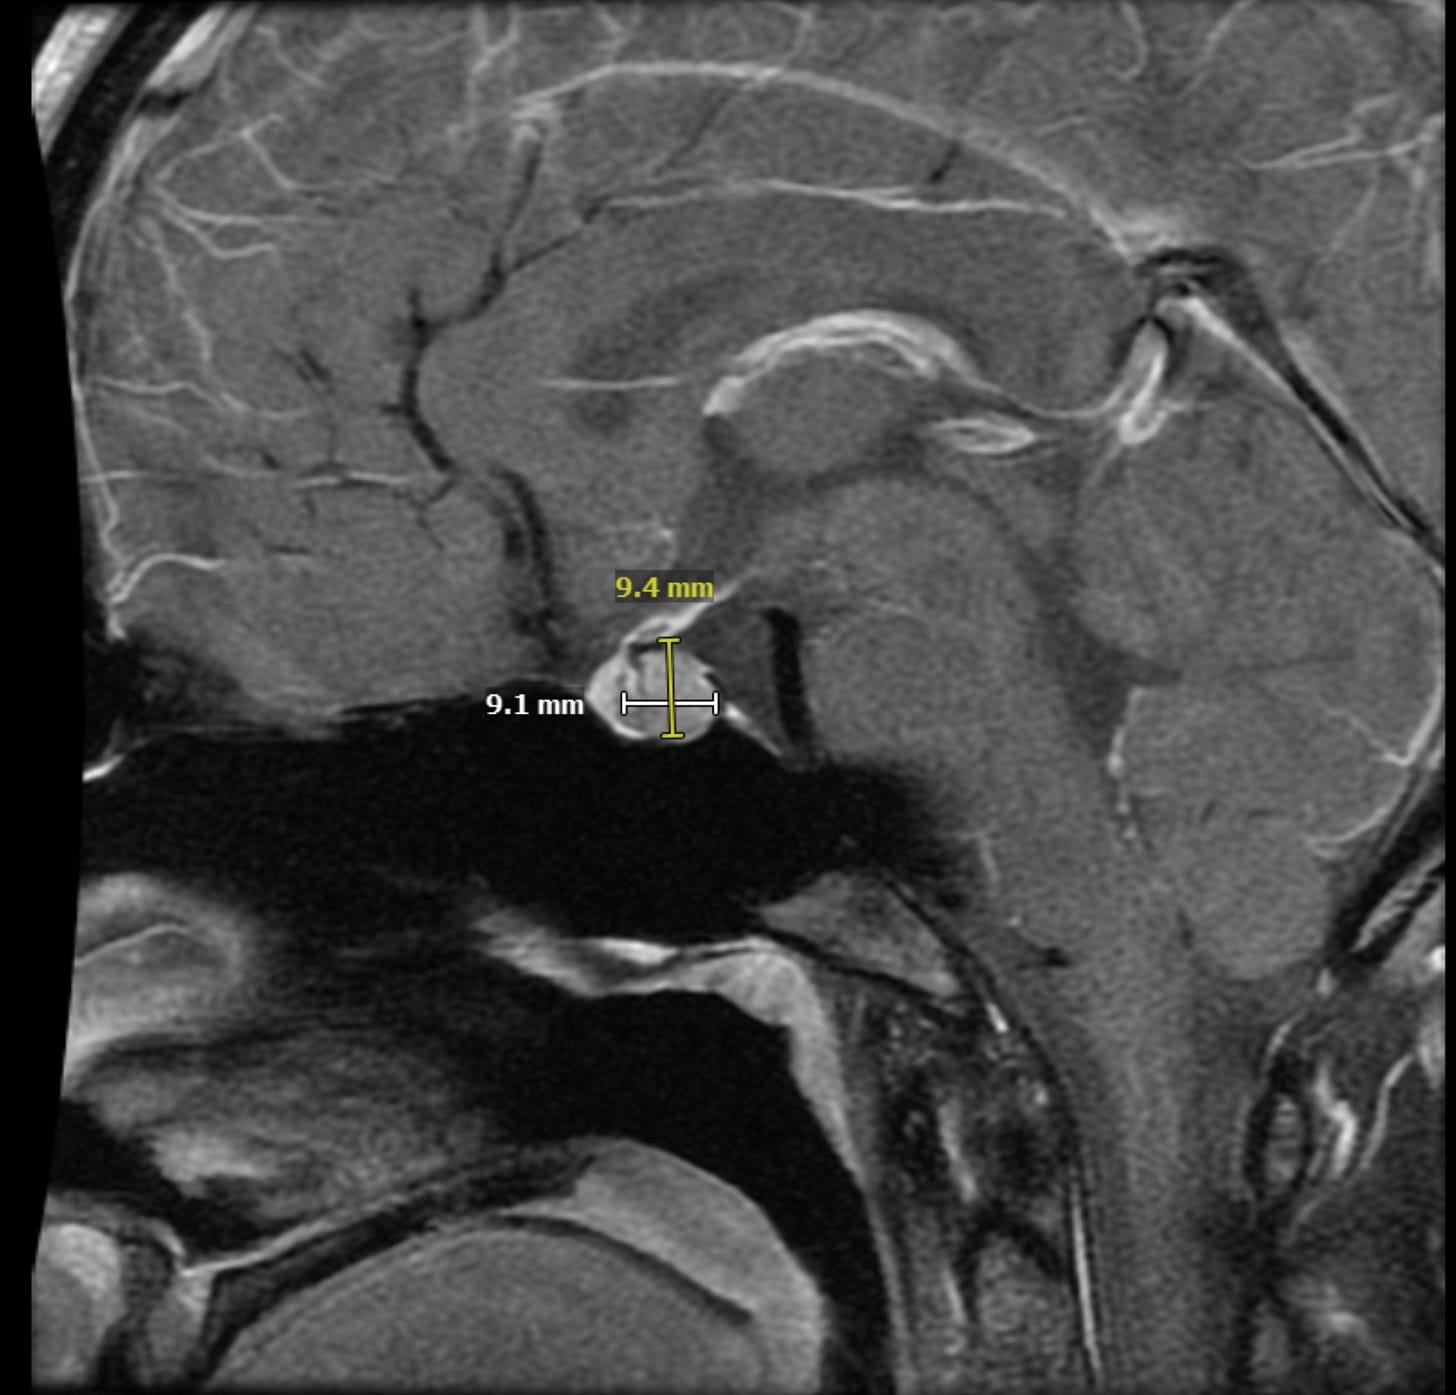

Amy has a prolactinoma: a tumor of the pituitary gland that causes the body to massively overproduce prolactin. Prolactin is best known for helping mammals produce milk for their babies, but is involved in hundreds of processes, including menstruation. Clinicians often call it “chill,” because it usually doesn’t spread and often responds to dopamine agonists like Cabergoline.

Her prolactin levels were supposed to be between 5–20 ng/mL. They were 330 ng/mL. The tumor was large, caught late, and growing quickly on the back of her posterior pituitary gland. Normally, you can try Cabergoline for a few months to see if it shrinks the tumor and lowers your prolactin. But according to her care team, if the tumor grew by even 20%, it would threaten her vision.

The first surgery removed 80% of the tumor. Her prolactin levels decreased from 330 ng/mL to 60 ng/mL. Not quite the 100% cure we were hoping for or the acceptable 5-20ng/mL range, but her condition appeared more manageable.

But Amy’s tumor continued to grow rapidly and had granulated features that made it more likely to spread if untreated. Within weeks of surgery, her prolactin rose again to 100 ng/mL. The prolactinoma neuroendocrinologist warned us that he had seen patients with similar tumors who now faced surgery #4 and radiation treatment #6. Medication was technically an option, but given the information we were provided, it felt like suicide.

This time, her level was 65ng/mL. Higher than after the first surgery.

Since Amy’s second surgery, we’ve spoken with most of the world’s leading prolactinoma experts. Yet even they disagree: some see residual tumor in Amy’s post-op MRIs; others don’t. Some advise cabergoline; others recommend a third surgery. The uncertainty is maddening, but at least they all agree it hasn’t spread.